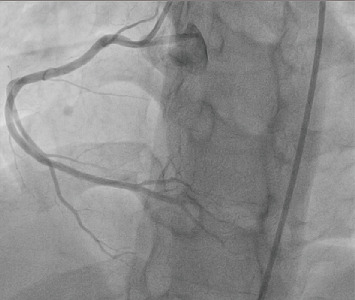

Overconsumption of energy drinks containing high levels of caffeine has been increasingly linked to cardiovascular morbidity and mortality. This case report describes a 24-year-old Caribbean-Black male with no prior comorbidities who experienced an aborted sudden cardiac death (SCD) after a recent energy drink binge a few hours prior to his ventricular fibrillation (VF) cardiac arrest. Primary percutaneous coronary intervention (PPCI) was successfully performed for a dreaded widowmaker lesion, thought to have arisen as a sequela of his excessive energy drink intake. The clinician should be cognizant of the major adverse cardiovascular events (MACEs), such as acute coronary syndromes (ACSs) and lethal arrhythmias, implicated with energy drink consumption.